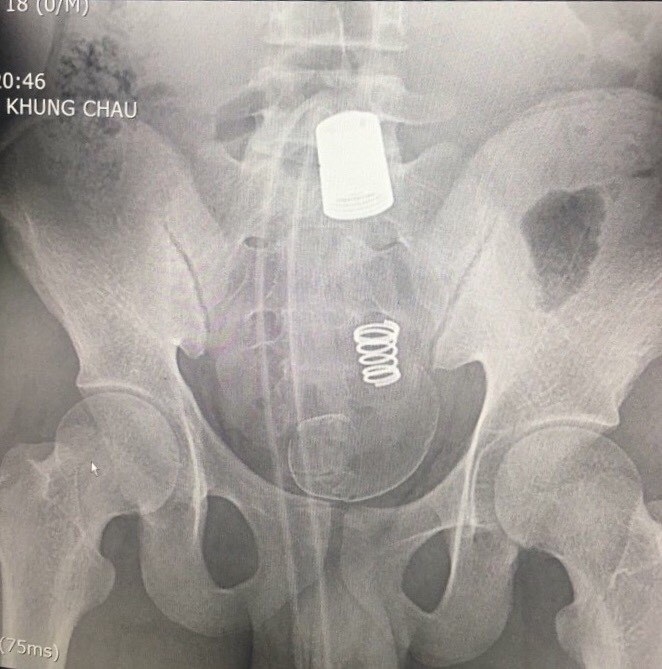

Sau khi tiến hành chụp X-quang, các bác sĩ phát hiện có hình ảnh dị vật cản quang rất lớn trong ổ bụng. Qua hỏi bệnh và thăm khám bệnh nhân kể khi đi đại tiện sử dụng vòi xịt vệ sinh, trong quá trình xịt rửa, phần hậu môn co thắt làm vòi xịt đi sâu vào hậu môn trực tràng không kéo lại được. Vì thế, bệnh nhân tự dùng dao cắt rời đoạn vòi nước và đến viện ngay sau đó.

Hình ảnh dị vật trên phim chụp X-quang. Ảnh: BS cung cấp.

BS Vinh cho biết, qua thăm khám hậu môn cho thấy dị vật hình ống silicon, rất chắc và không thể lấy ra được qua đường hậu môn. Dị vật cũng gây nên tình trạng chảy máu niêm mạc đường ruột.

Vì thế, sau khi hội chẩn, các bác sĩ quyết định phẫu thuật lấy dị vật cho bệnh nhân. Kíp phẫu thuật đã mở bụng, mở đại tràng sigma lấy được cả đoạn vòi nước và đầu xả dài khoảng 45 cm.